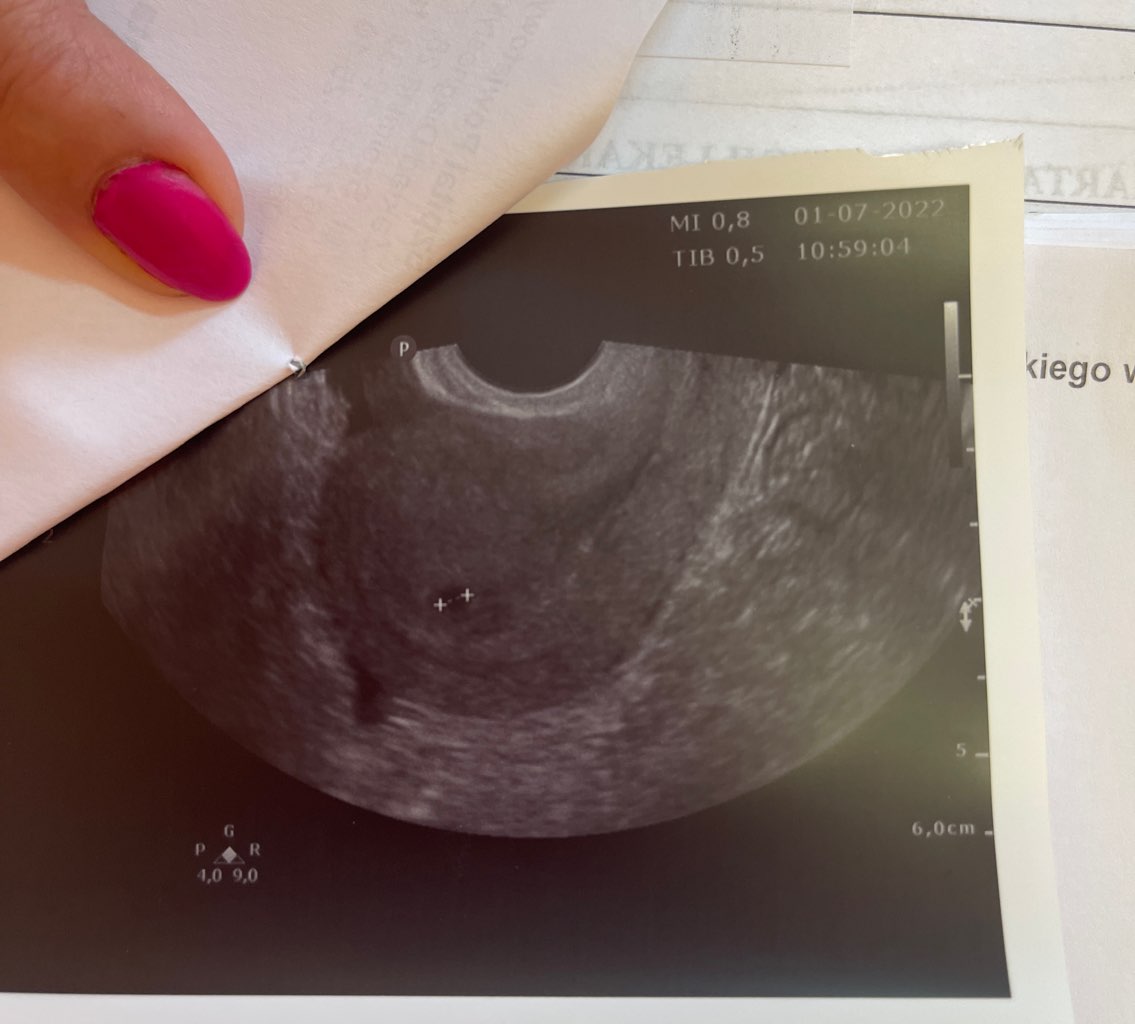

Według @ dziś 5t6d ciąży, będąc w 4 tygodniu trafiłam do szpitala z podejrzeniem CP przez znaczna ilość płynu w zatoce douglasa, wykonali laparoskopię i okazało się ze się mylili, na drugi dzień pojawił się pęcherzyk w macicy Malutki ale się pojawił, a płyn który był usuniety dzień wcześniej pojawił się ponownie (płyn surowiczy). Dodam ze czuje się dobrze, plamienia nie było i nie ma.

Pierwsze usg mam w poniedziałek 11ego bo będąc w szpitalu powiedzieli mi ze nie ma sensu robić szybciej bo i tak nic nie będzie. Poszłabym najchętniej jutro ale mieszkam w małej miejscowości gdzie nie ma szans na wizytę w weekend.